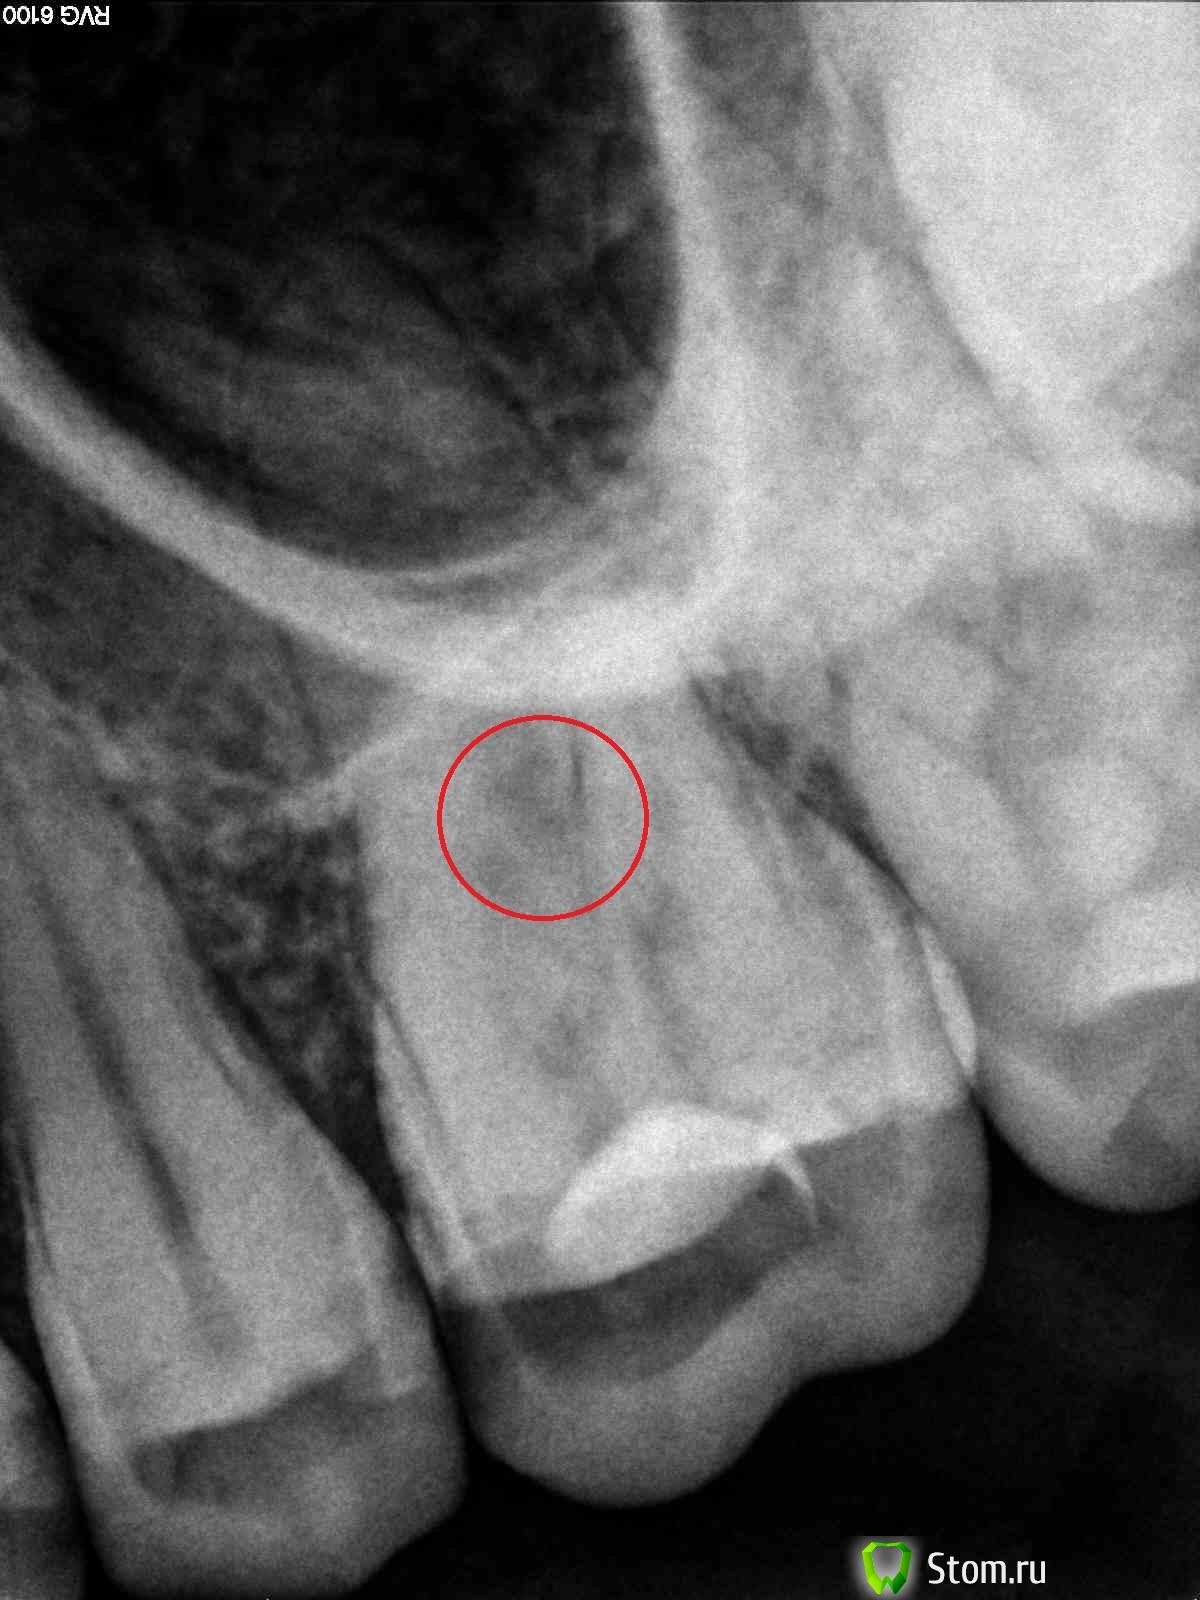

kurt Опубликовано 14 марта, 2012 Автор Поделиться Опубликовано 14 марта, 2012 сегодня получилось очно пообщаться с врачом и вот какое предположение он высказал, что на 1м снимке до лечение уже видно (выделил красным на снимке), что зуб уже в области дна был заражен кариусом и врач, когда сверлил был вынужден сделать перфорацию, чтобы удалить пораженные ткани... какое Ваше мнение - действительно могло так быть? и врач просто вынужден был сделать перфорацию? и вот еще статья "Закрытие перфораций в области фуркации корней зуба с использованием цемента МТА ", клинический случай №1 (не сочтите за рекламу сайта, т.к. не нашел больше, где она представлена!), где описана процедура по "спасению" зуба с перфорацией дна - можно такую же методику применить и с моим зубом, если его перфорация все же подтвердится? заранее мои благодарности!!! Ссылка на комментарий

samsonov Опубликовано 14 марта, 2012 Поделиться Опубликовано 14 марта, 2012 Эта красная зона не совсем однозначно трактуется как перфорация(простите за повторенье).Условно,перфорации лечатся. Ссылка на комментарий

Salma Опубликовано 14 марта, 2012 Поделиться Опубликовано 14 марта, 2012 Судя по более раннему снимку там все таки перфорация.как вам выше написали,зуб с перфорацией можно восстановить,но прогноз зуба не очень благоприятный Ссылка на комментарий

samsonov Опубликовано 14 марта, 2012 Поделиться Опубликовано 14 марта, 2012 Скажем так,кариозные монстры обычно ползут от жевательной поверхности к корням,а не наоборот.При живой пульпе поражение трифуркации корней маловероятно... Ссылка на комментарий